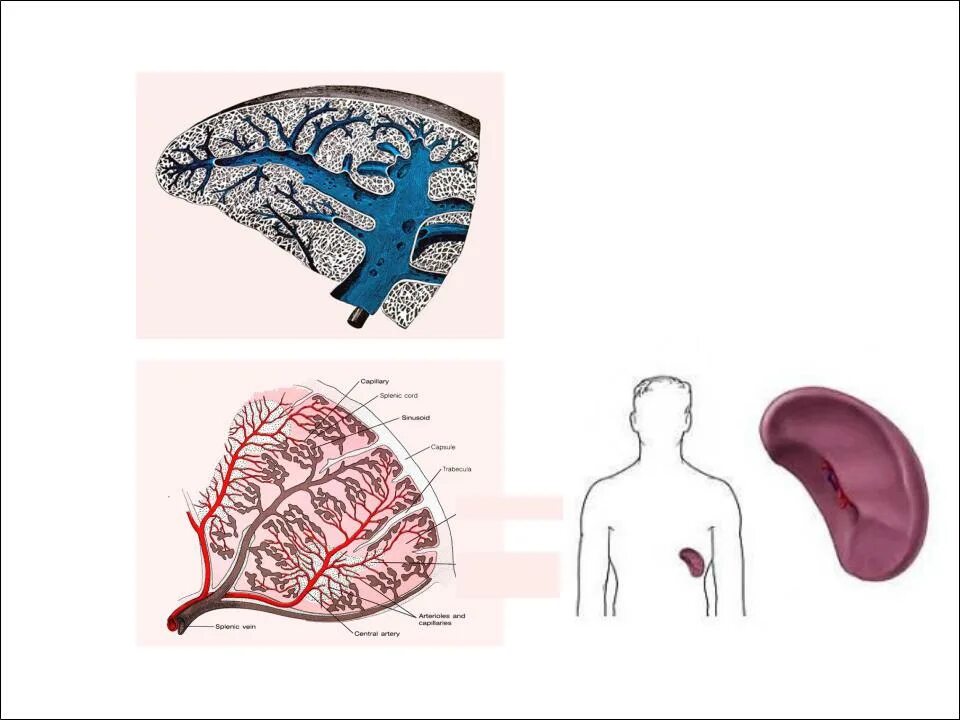

Уменьшение селезенки